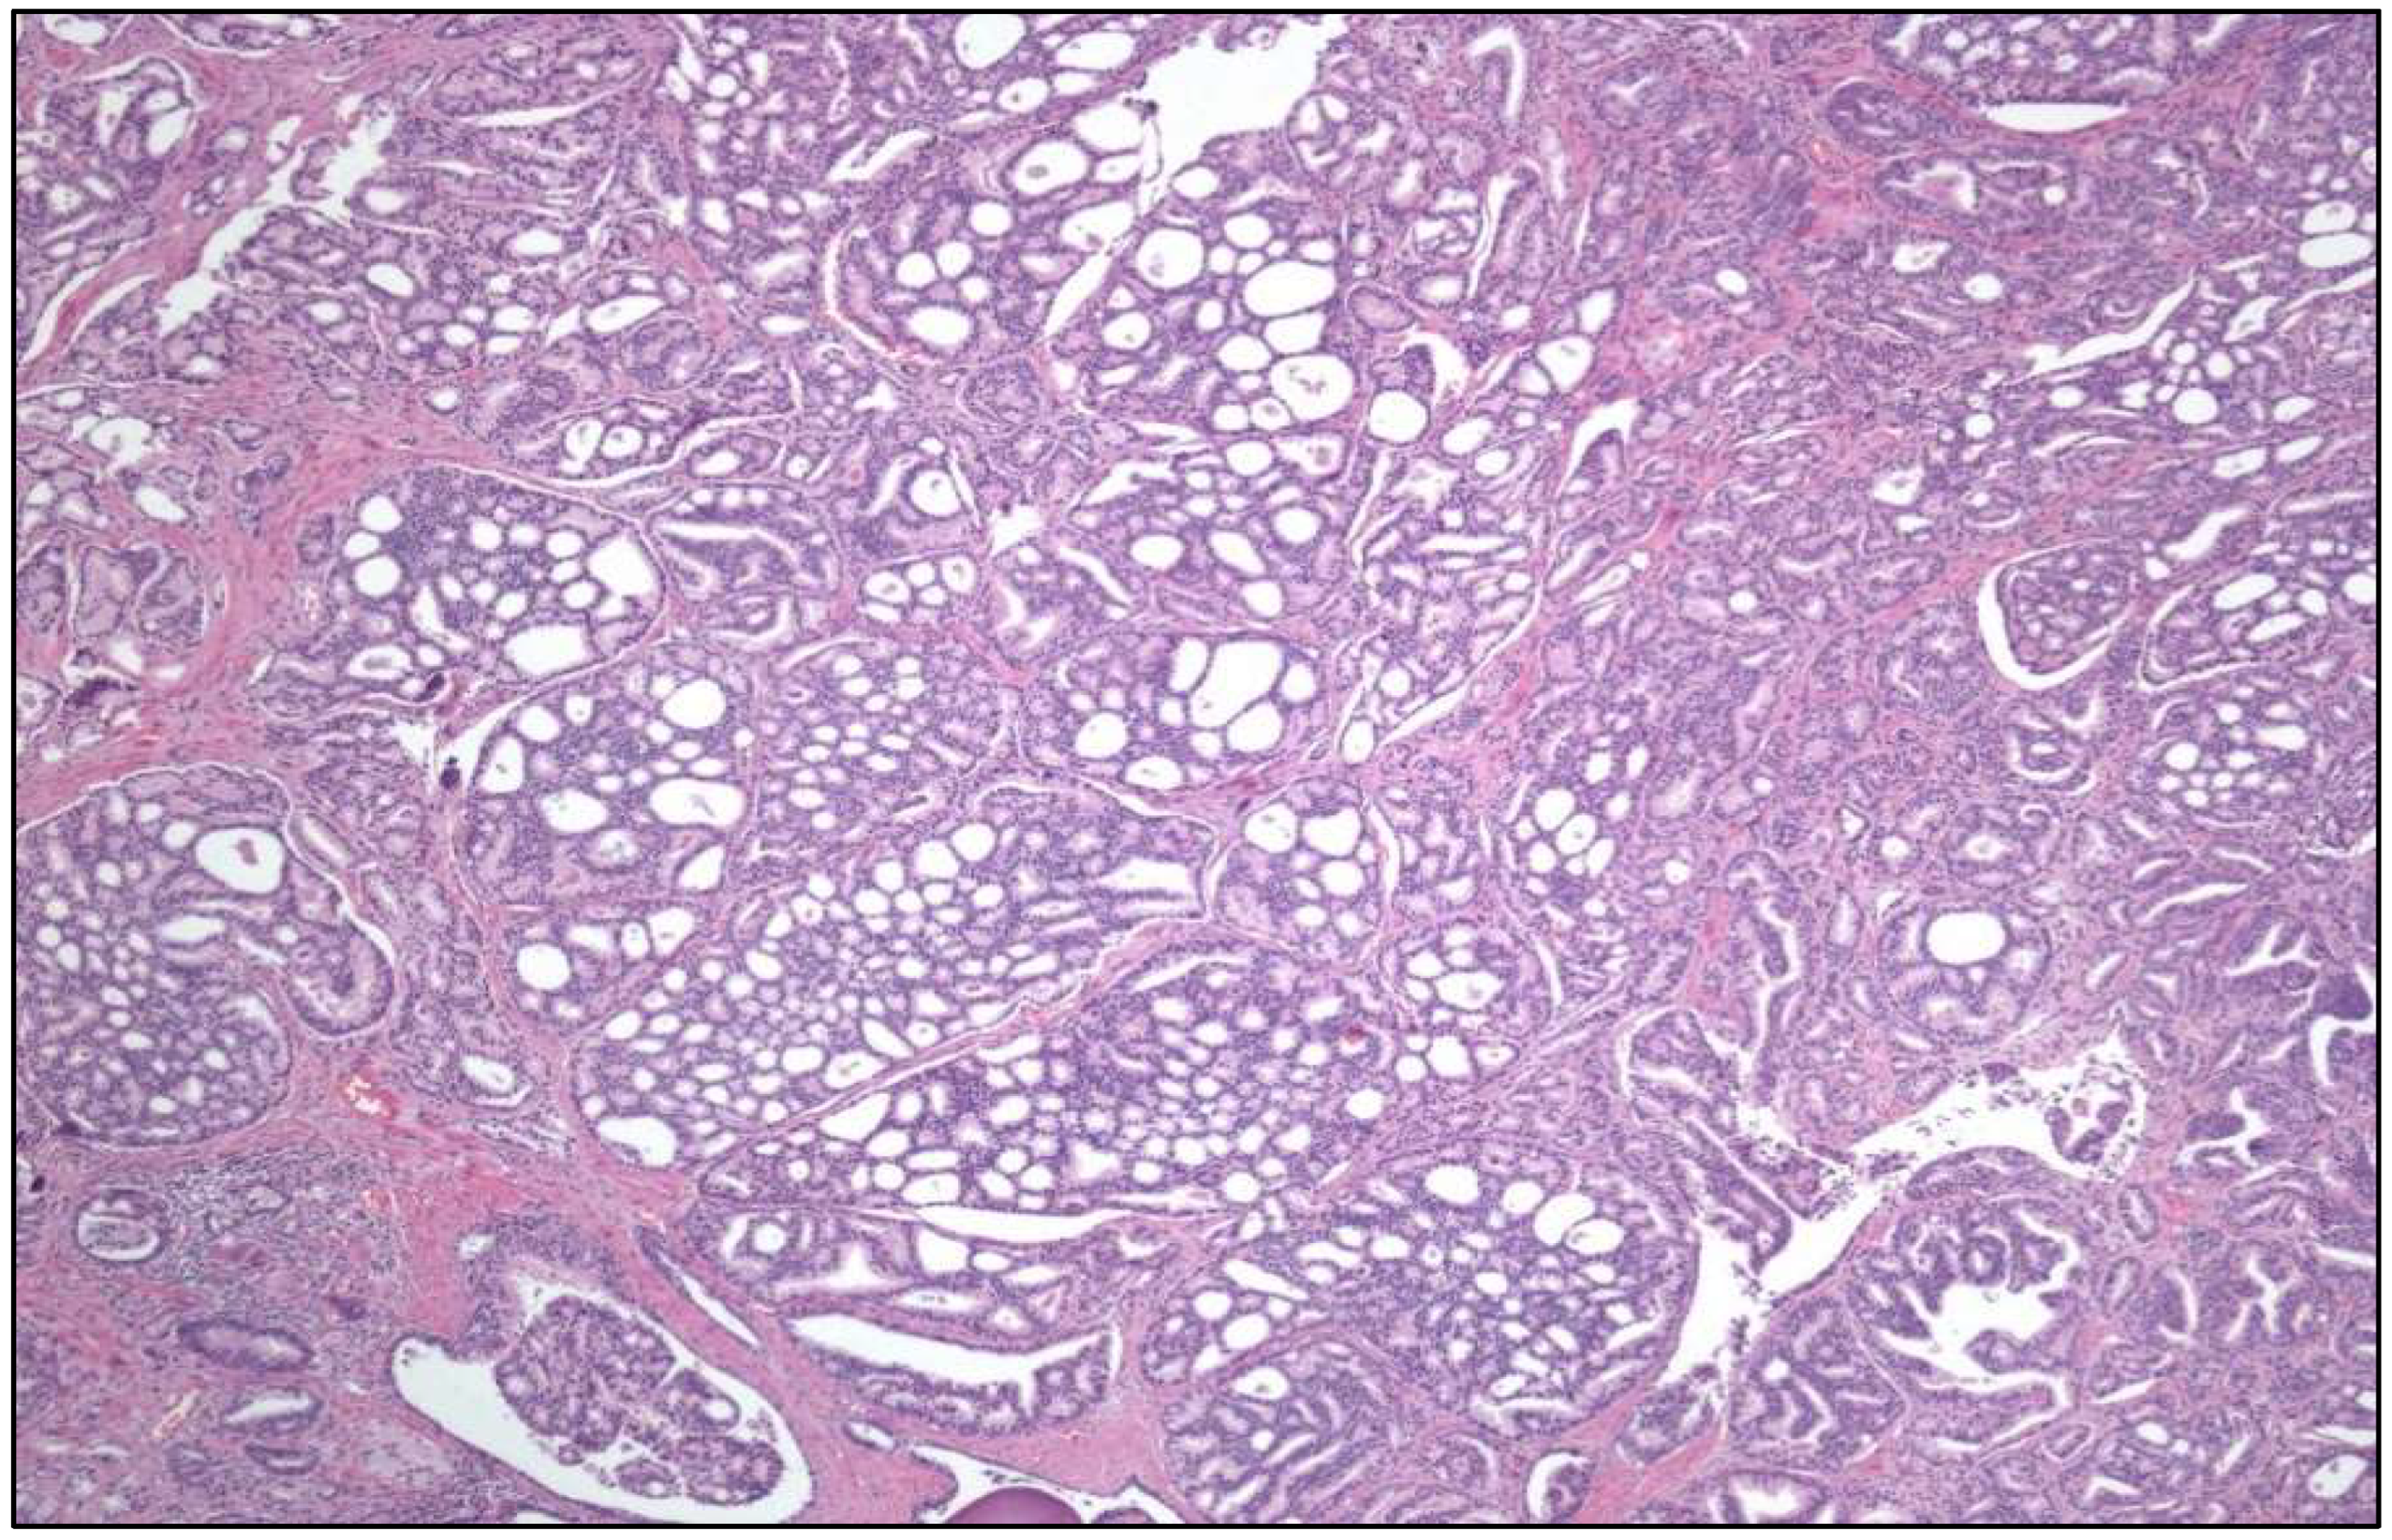

- Large “nested” UC (Figure 3)

- Clear cell UC is renamed as “glycogen-rich” clear cell UC (Figure 3) to distinguish it from the adenocarcinoma of Müllerian type.

- Glandular, squamous, trophoblastic (Figure 3), Müllerian, and neuroendocrine morphologies must be specifically mentioned in the pathological report of UC, including its approximate percentage.

- Micropapillary, plasmacytoid (Figure 3), and other “wolves in lamb clothes” must be recognized and specifically reported, either pure or mixed, in the pathological report of UC.